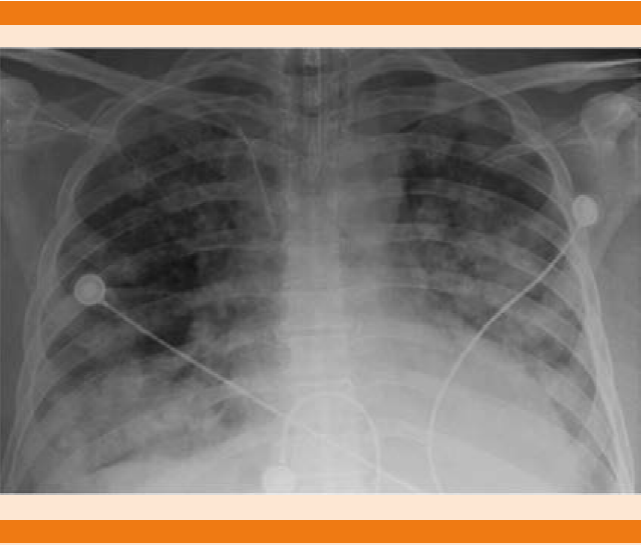

Wegener Granulomatosis Radiology Case Radiopaedia Org

Wegener Granulomatosis Radiology Case Radiopaedia Org from prod-images-static.radiopaedia.org. Para más información pulse aquí para ir al website.